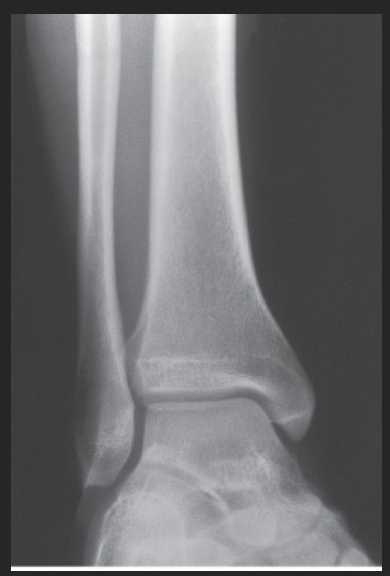

Name this projection.

What type of projection is it?

Which side is the patient turned toward?

Where does the CR enter?

How do you evaluate for a true lateral?

The tibiotalar joint will be well visualized, and the fibula will be over the posterior half of the tibia

How much of the distal tibia and fibula must be included?

Which joint is well visualized?